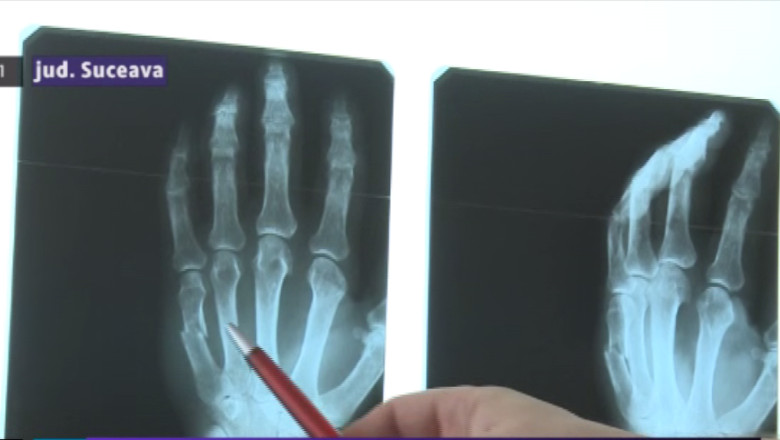

„Agresivitatea era ieşită din comun şi fără să fie provocată. Doamna biolog trecea pur şi simplu pe hol ca să-mi aducă la camera de gardă nişte analize. Am strigat la acel pacient, îndreptând astfel atenţia lui înspre a mea. Din încercarea de a para nişte lovituri m-am ales cu o fractură de mâna dreaptă”, povestește Constantin Păncescu, medic chirurg.

„Fiind chirurg, mâna dreaptă fiind mâna cu care operează, cu care instrumentează, are nevoie să îşi recapete dexteritatea şi chiar dacă din punct de vedere ortopedic va putea să renunţe la ghips după o lună, după 28 de zile, cel puţin două săptămâni are nevoie de recuperare. Deci o lună şi jumătate este să zicem relativ optimist”, a declarat Tiberiu Brădăţan, purtătorul de cuvât al Spitalului Judeţean Suceava.